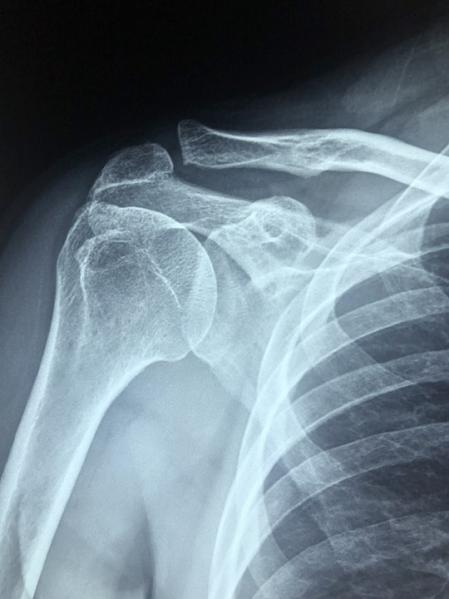

La factura correspondía principalmente a una radiografía, por lo que Osman decidió crear su propia máquina de rayos X para no tener que hacer frente nunca más a unas sumas tan elevadas de dinero, lo que le llevó a la siguiente pregunta: ¿podría fabricar su propia máquina de rayos X por un precio más barato de lo que le cobraron?

Para ello usó: un tubo de rayos X de 115 dólares, que consiguió de una máquina de rayos X dental rota que compró en eBay; un rollo gigante de hoja de plomo; varios contenedores Geiger y un suministro eléctrico capaz de suministrar hasta 60.000 voltios.

El resultado fue un éxito, la construcción de su propia máquina de rayos X le costó mucho menos que la factura de una sola radiografía en el hospital. Eso sí, el propio Osman ha querido advertir de los peligros de hacerse radiografías en casa: "¿Quieres llenarte de radiación?", y añadía que "Este es el artilugio más peligroso que he construido".